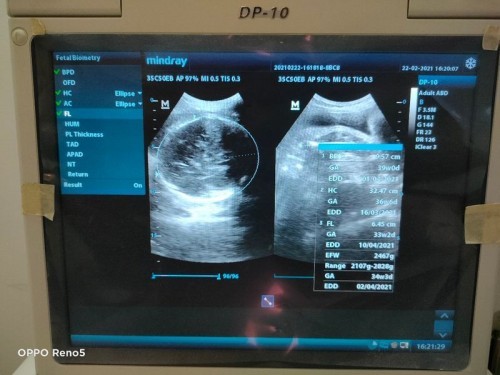

Malam bunda semuanyaa 😊 Ada yang hplnya awal bulan april gak ? Udah ngerasain apa aja bun ?, Kalo aku sering ngerasain perut kenceng, sering bak dan bab, kaki sama tangan pada bengkak, mau bangun dan jalan aja susah karena pegel dan sakit :-( Doain yaa bun supaya secepatnya dapat sinyal cinta dari dede bayi 🤗🤲 Oiya mau tanya tentang konpal itu kaya gimana yaa ? #seriusnanya #bantusharing #ingintahu #jangandibully